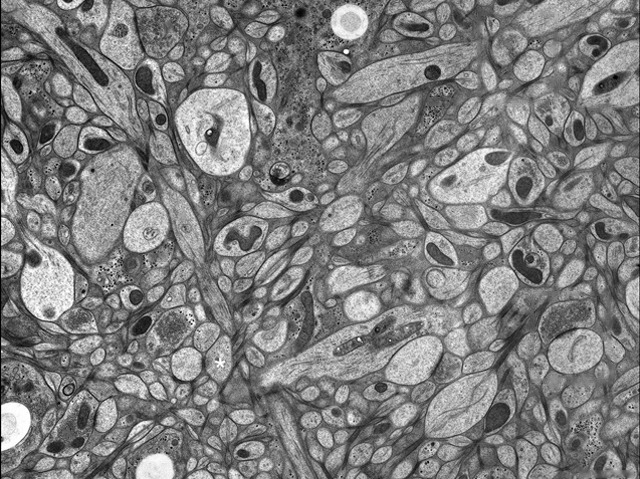

Reactions are never quite ‘lightning quick’ because impulses flashing along nerve channels must hurdle the tiny gaps, or synapses, between neurons. Chemical messengers – neurotransmitters – are stored at synapses in tiny pods called vesicles, some of which are primed to release their cargo in an instant to speed an arriving impulse across the gap. Recent advances in 3D microscopy have enabled this hair-trigger mechanism to be studied in detail. Scientists used this picture of a section of mouse’s brain to locate the position of synapses, then looked inside them to observe vesicles fusing with neuron membranes and breaking open. Further experiments identified several proteins controlling this process. This research is important to the understanding of a range of illnesses associated with the malfunction of synapses, including Parkinson’s disease.